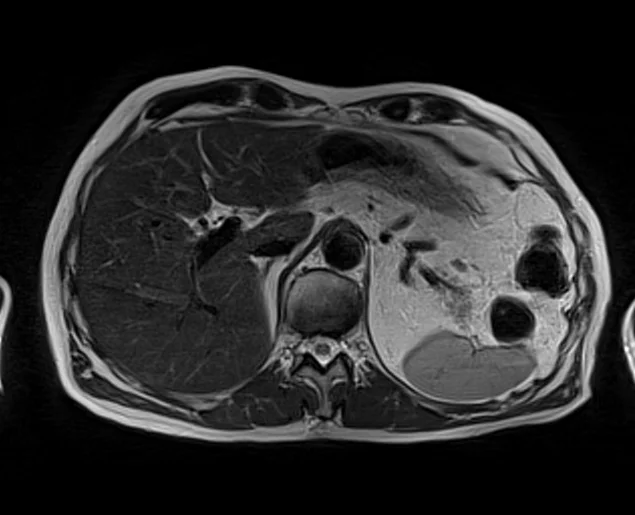

mrimaster

t2 2 - MRI